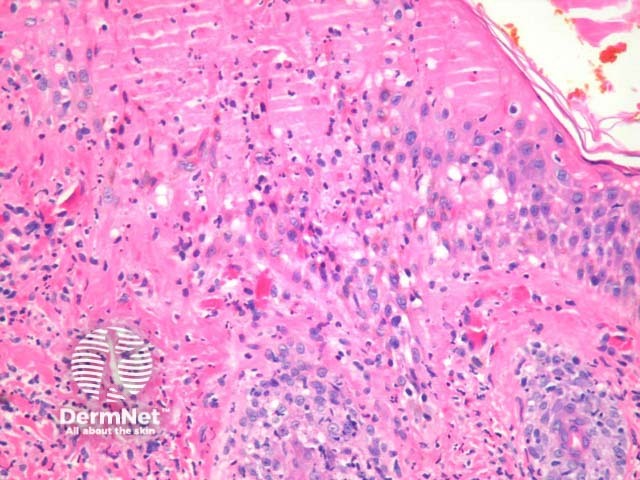

In hydroa vacciniforme, sections show epidermal spongiosis, vesiculation and necrosis overlying a dense dermal infiltrate (figure 1). The necrosis may be confluent (figures 2, 3) and infiltrated by a mixture of acute and chronic inflammatory cells. In older lesions there may be scarring.

Figure 2